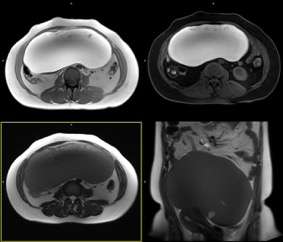

圖1 卵巢內膜樣囊腫 T1WI及T1WI脂肪抑制序列以高信號為主,T2WI以低信號為主,內部有少許其它信號病變,為出血不同時期的表現。